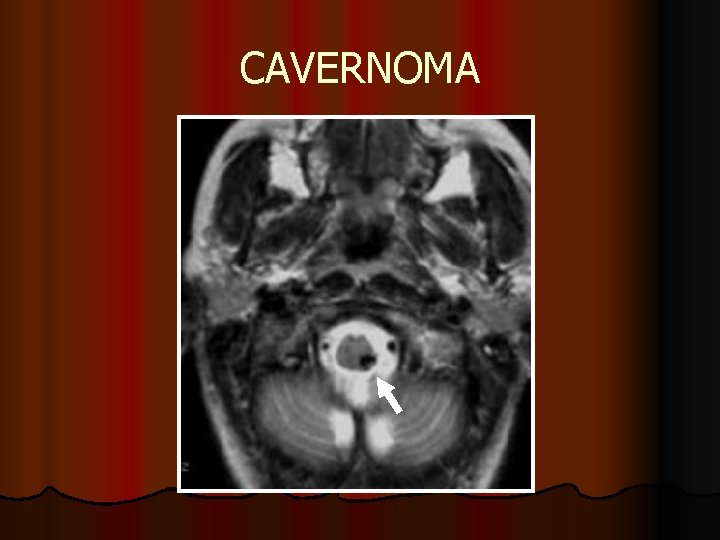

CAVERNOMA